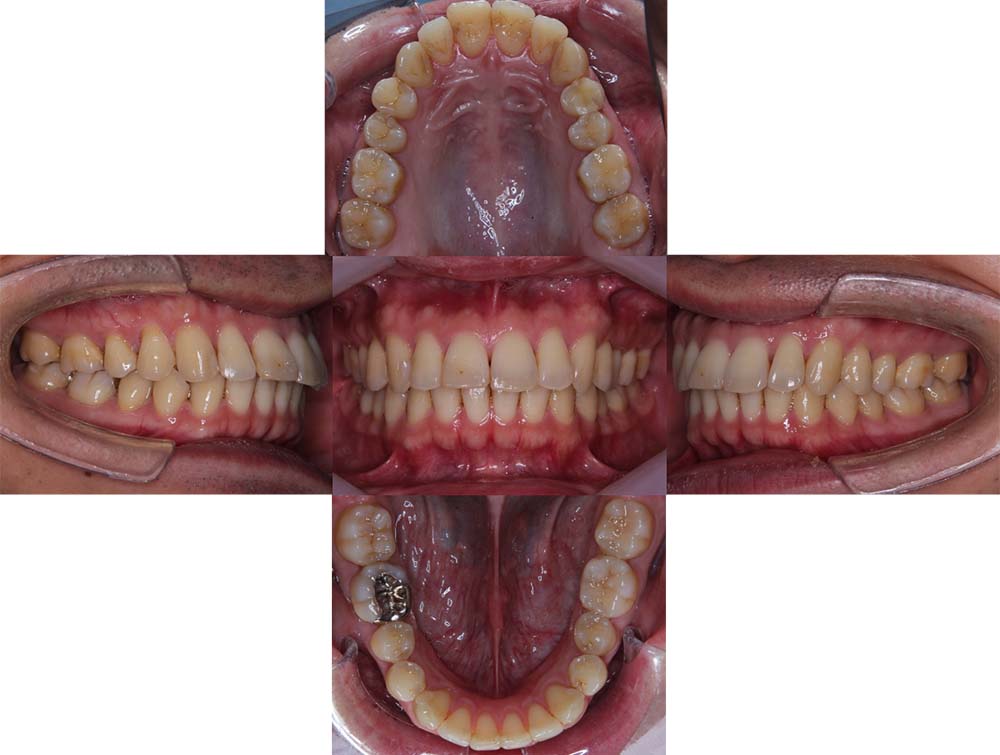

症例03

| 主訴 | 歯並びがガタガタしている。 |

| 診断名あるいは主な症状 | 過蓋咬合、叢生 |

| 年齢/性別 | 26歳・女性 |

| 矯正ステージ | 大人の矯正治療 |

| 治療方法 |

ワイヤー矯正 歯科矯正用アンカースクリュー(3本) |

| 抜歯部位/抜歯有無 | 抜歯 |

| 治療内容 | 上下顎の奥歯を後方に移動後、ガタガタの改善と上下顎前歯を後退させた。 |

| 費用 |

90万円程度(2025.10時点の料金となります。) ※矯正基本料金、アンカースクリュー、審美ブラケットを含む |

| 治療期間 | 2年8ヶ月 |

| 主なリスク・副作用 | 痛み、歯根吸収、歯肉退縮、虫歯、後戻り |